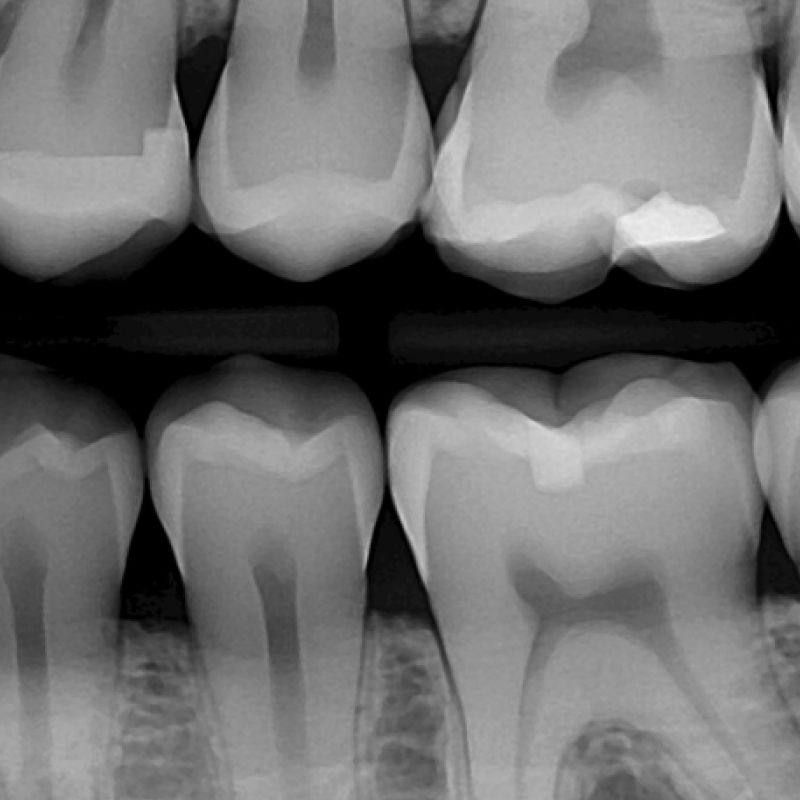

The American Dental Association just issued a formal evidence-based recommendation to stop using lead aprons (X-ray shields) because modern digital dental X-rays really are that safe. And, higher levels of radiation are harmful, so people are concerned.

There is still no other technology for imaging tooth roots and the surrounding bone.

Yet, dental X-rays are not very accurate for diagnosing cavities. There are other options without use of radiation. Near infrared, optical coherence tomography, transillumination, and liquid contrast agents are nearly as useful. We have these technologies, and are happy to offer them as a supplement generally, and as an alternative specifically for anyone who would otherwise not access care.